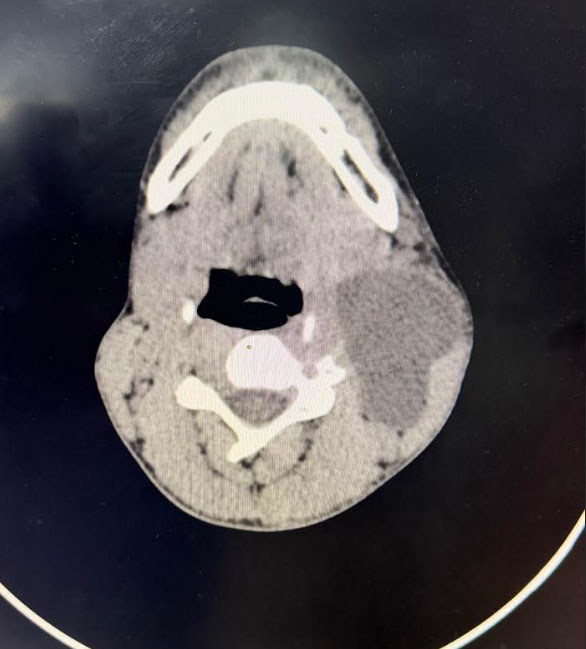

To evaluate the extent of the mass and plan the surgical approach, a CT scan of the neck was performed. The imaging provided clear, actionable data:

• Dimensions:Approximately 8 cm x 6 cm.

• Characteristics:A well-defined, unilocular cystic mass.

• Impact:Due to its significant size, the cyst was causing medial displacement of the surrounding neurovascular structures.